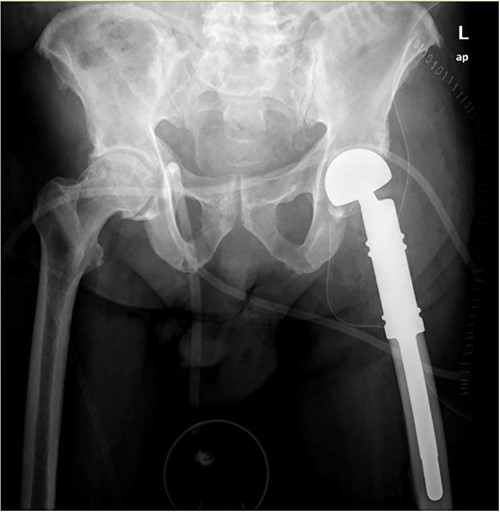

Wide intra-articular tumor resection of the proximal femur and reconstruction with tumor prosthesis and bipolar head were indicated (Fig. 4).

Wide intra-articular tumor resection of the proximal femur and reconstruction with tumor prosthesis and bipolar head.